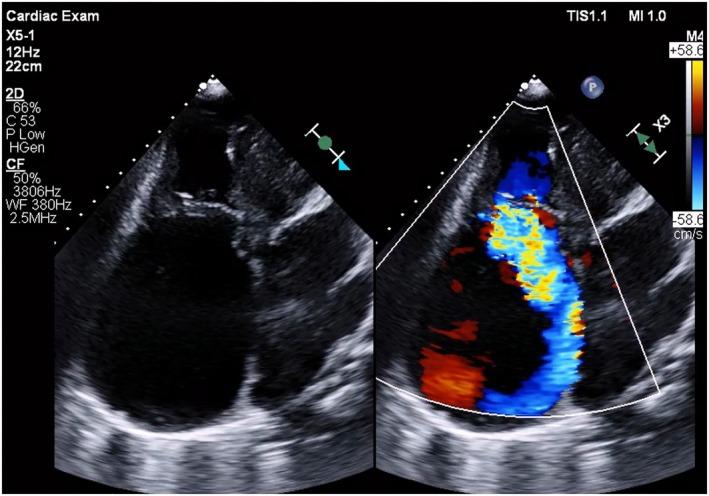

Leadless pacemaker implantation in a patient with severe right atrium dilation was unsuccessful using the conventional approach. The delivery system failed to gain sufficient backup force from the atrial wall and moved upward within the dilated atrium. To overcome this, the snare technique was employed. By securing the slightly distal portion of the top of the shaft curve, the pushing force was effectively transmitted to the tip of the system, creating a stable gooseneck shape for successful implantation.

对于一名患有严重右心房扩张的患者,采用传统方法进行无导线起搏器植入未成功。输送系统未能从心房壁获得足够的支撑力,在扩张的心房内向上移动。为克服这一问题,采用了圈套技术。通过固定轴曲线顶部稍远的部分,推力有效地传递到系统尖端,形成稳定的鹅颈形状,从而成功植入。